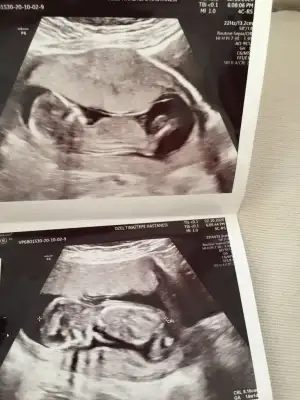

neyse baktı etti dedi kız gibi ama net göremiyorum yüzüstü duruyor dedi ama net kız diyemem dedi bekle 16yı dedi sağolun dedim

bekleyin kızlar gibilerle kafa daha çok karışıyor bide siz bakin bakim fikriniz ney☺